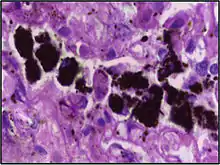

Micrograph showing hemosiderin-laden alveolar macrophages, as seen in a pulmonary haemorrhage. H&E stain.

Alveolar macrophages are frequently seen to contain granules of exogenous material such as particulate carbon that they have picked up from respiratory surfaces. Such black granules may be especially common in smoker's lungs or long-term city dwellers.